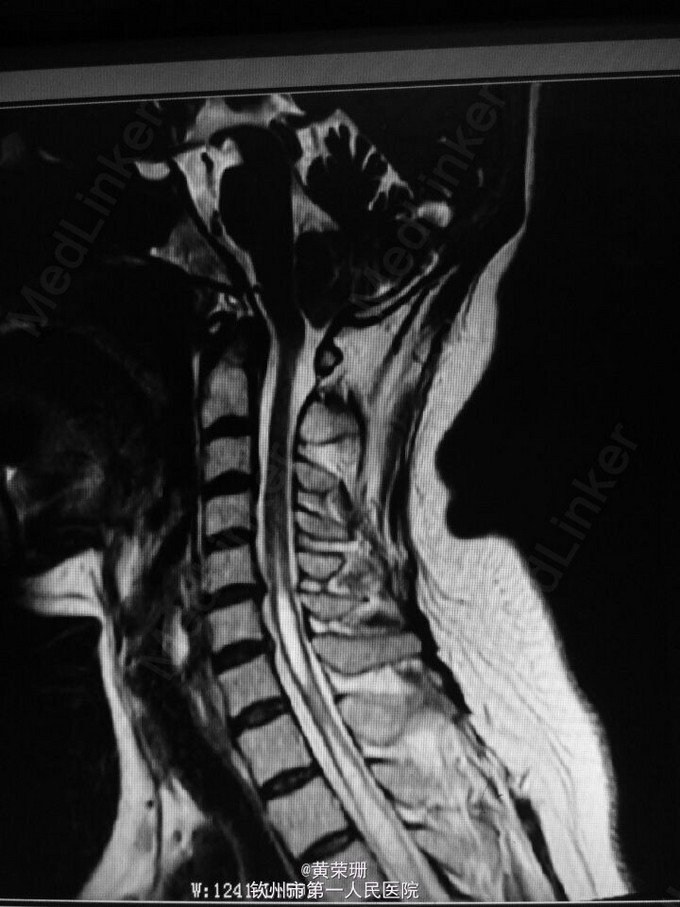

脊髓空洞症1例

黄医师   钦州市第一人民医院

52岁女性患者,既往有颈椎病史。诉反复头晕1月余,伴晕眩,平卧后起立时明显。查体:神清,言清,双上肢、下颌部浅感觉减退,右侧明显,双上肢腱反射(++),双下肢腱反射(+),肌力5级,肌张力正常。入院后行头颅+颈椎MRI发现脊髓空洞症。